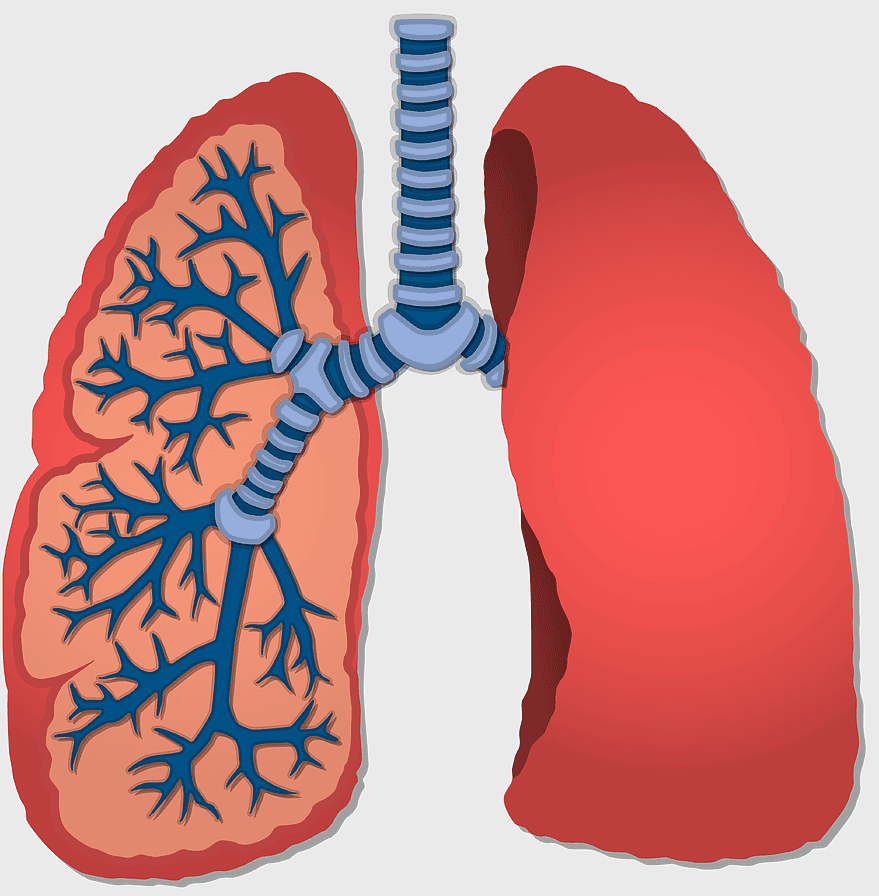

Pulmonary pleurae, Lung Tuberculosis, Pleural cavity, respiratory system, lung anatomy, medical illustration, pulmonary health, PNG

- Pulmonary pleurae

- Lung Tuberculosis

- Pleural cavity

- respiratory system

- lung anatomy

- medical illustration

- pulmonary health